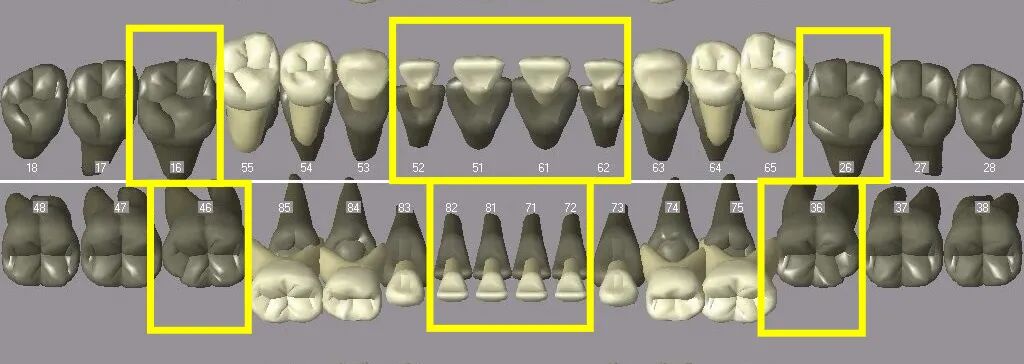

换牙这场“马拉松”,总体分为三程:

曲面断层片怎么看换牙与身高有关吗?关于孩子换牙的所有疑问一篇说清_https://www.jmylbn.com_新闻资讯_第3张

1. 第一程:从5-7岁开始,持续2-3年

曲面断层片怎么看换牙与身高有关吗?关于孩子换牙的所有疑问一篇说清_https://www.jmylbn.com_新闻资讯_第4张

曲面断层片怎么看换牙与身高有关吗?关于孩子换牙的所有疑问一篇说清_https://www.jmylbn.com_新闻资讯_第5张

图注:8颗乳前牙脱落,8颗对应的恒前牙萌出;4颗第一恒磨牙(六龄齿)直接萌出。

2. 第二程:从8-10岁开始,持续2-3年

曲面断层片怎么看换牙与身高有关吗?关于孩子换牙的所有疑问一篇说清_https://www.jmylbn.com_新闻资讯_第6张

曲面断层片怎么看换牙与身高有关吗?关于孩子换牙的所有疑问一篇说清_https://www.jmylbn.com_新闻资讯_第7张

图注:8颗乳磨牙+4颗乳尖牙脱落,8颗对应的前磨牙+4颗对应的恒尖牙萌出。

3. 第三程:一般10-12岁

曲面断层片怎么看换牙与身高有关吗?关于孩子换牙的所有疑问一篇说清_https://www.jmylbn.com_新闻资讯_第8张

曲面断层片怎么看换牙与身高有关吗?关于孩子换牙的所有疑问一篇说清_https://www.jmylbn.com_新闻资讯_第9张

图注:4颗第二恒磨牙直接萌出